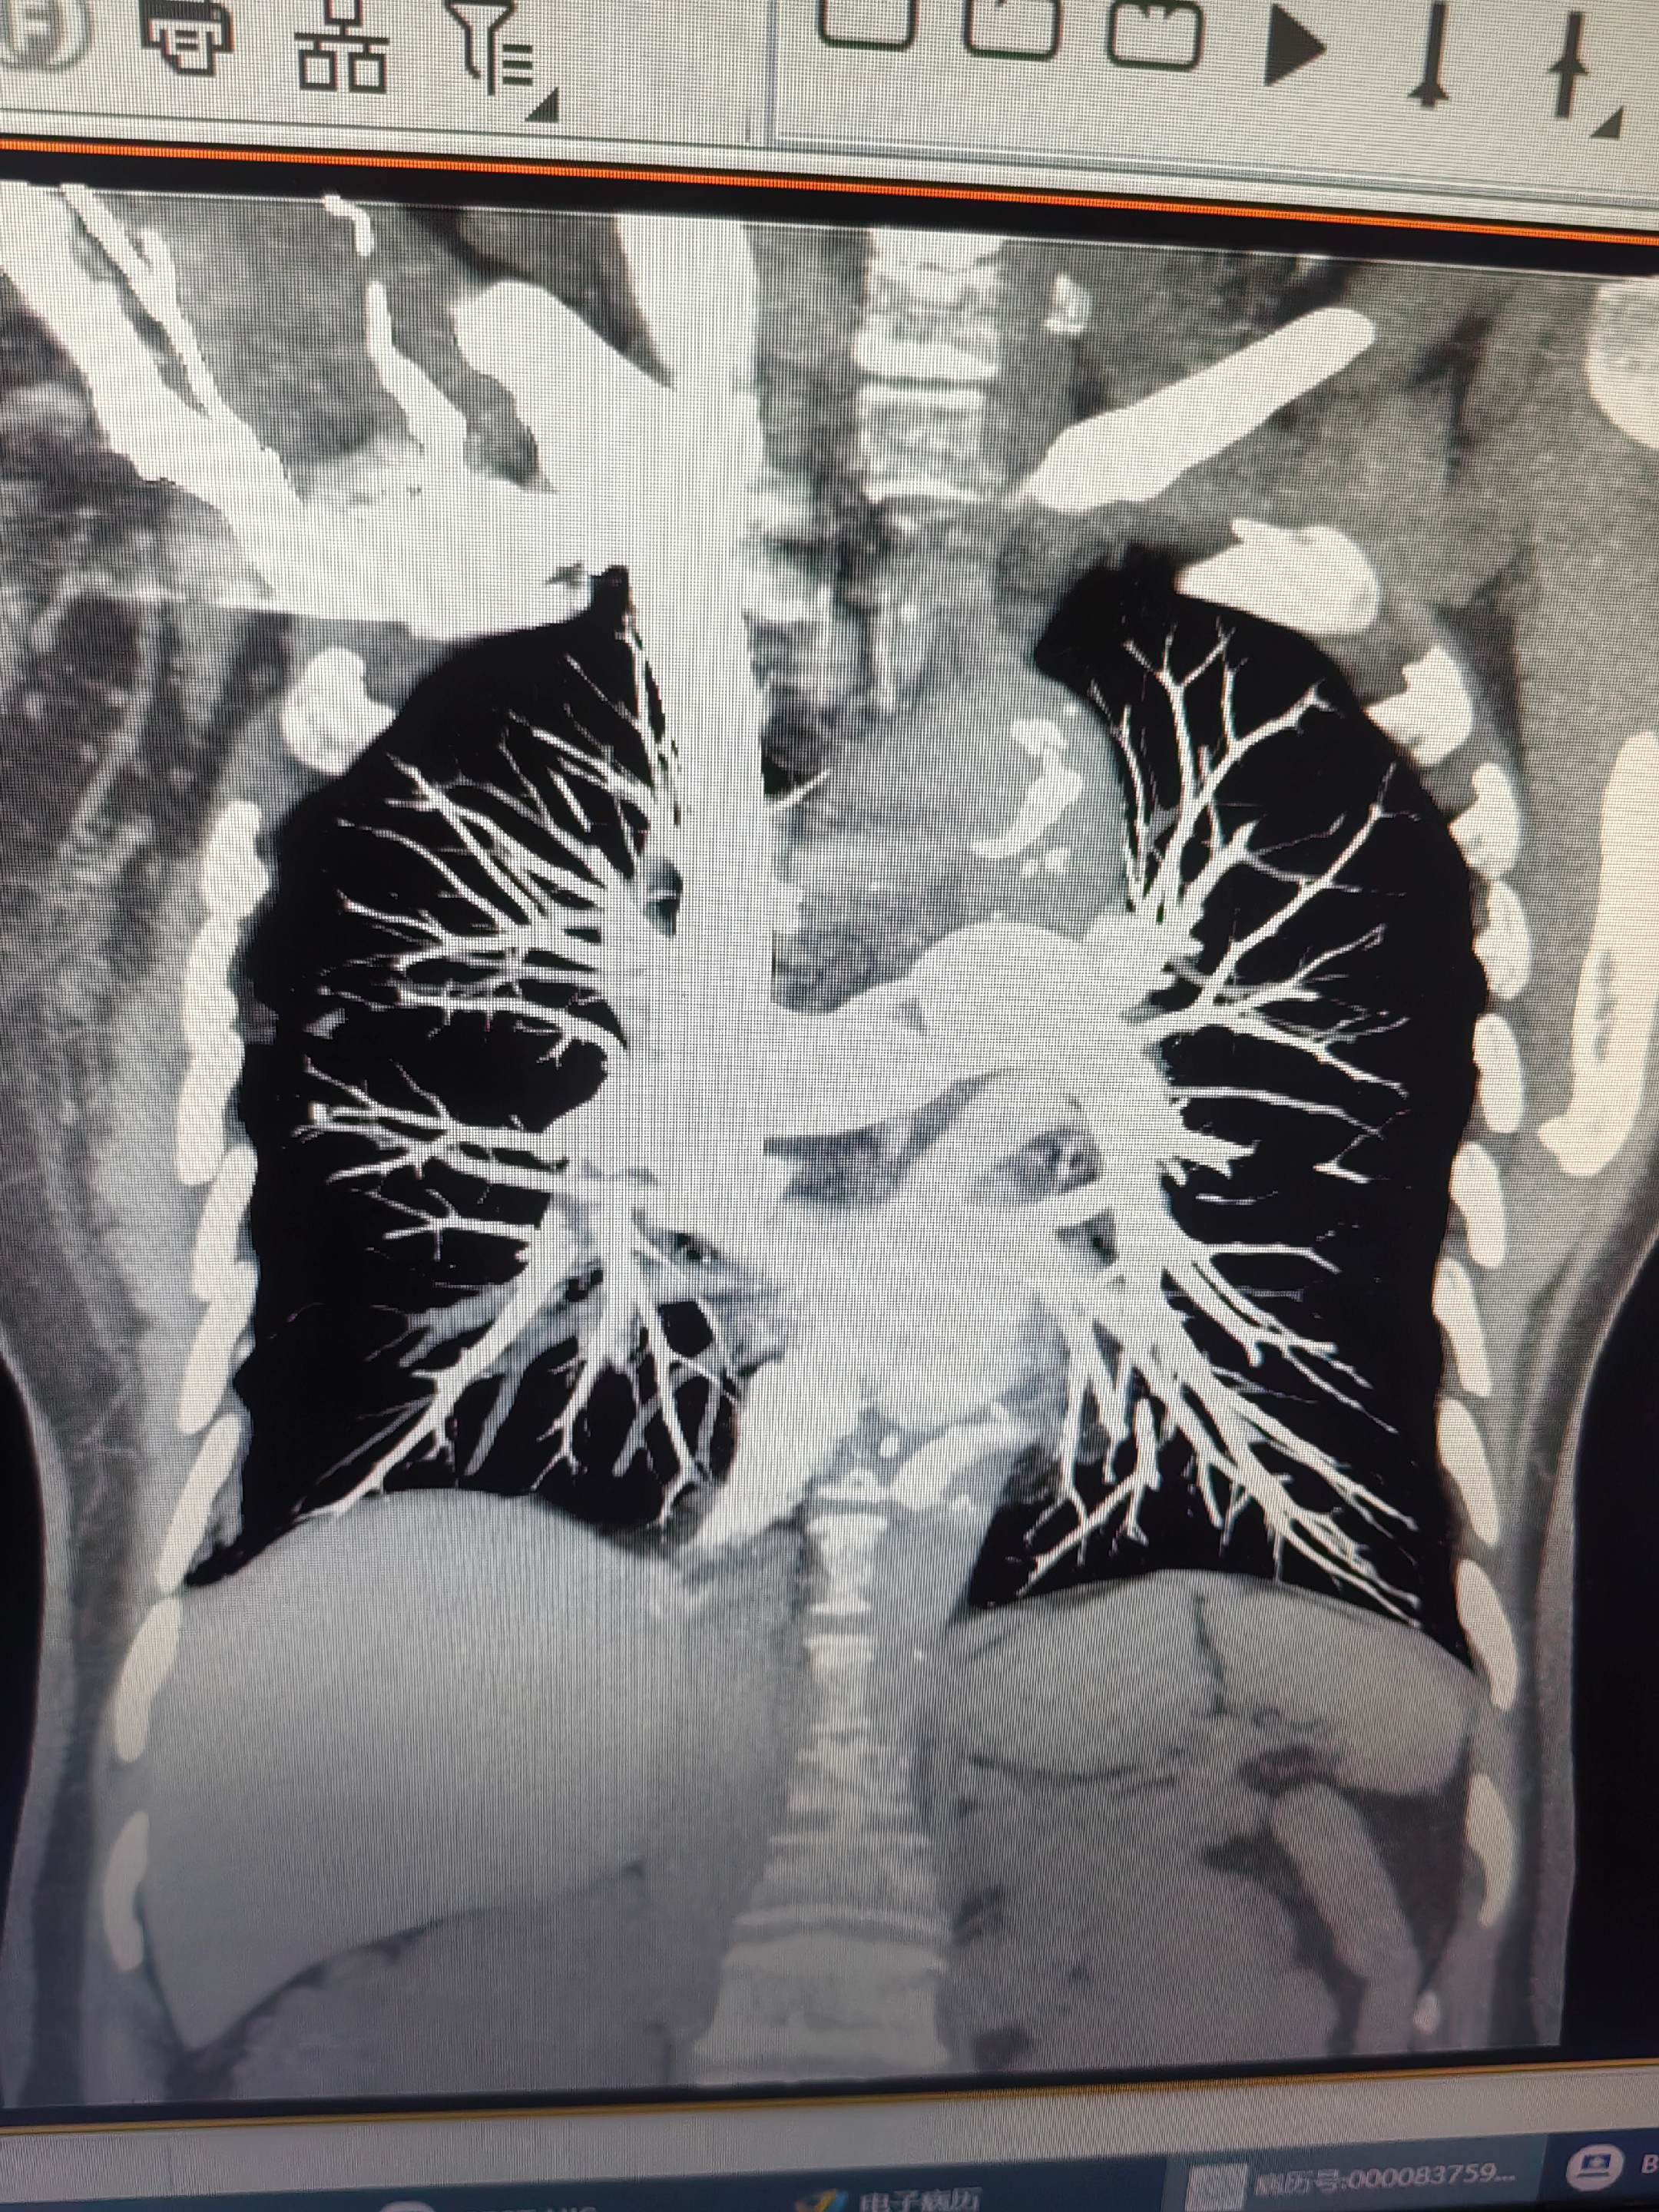

肺栓塞。